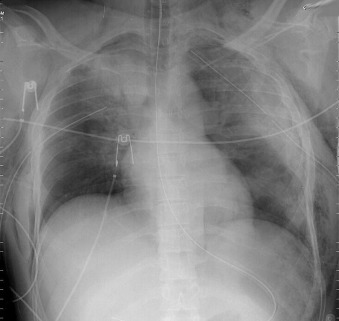

Of all traumatic lesions to the thoracic cardiovascular system, the most predictable one is blunt deceleration/acceleration traumatic injury to the thoracic aorta, resulting in a false aneurysm-type lesion, typically of the isthmus proximal descending aorta. It may also involve the ascending aorta, the supradiaphragmatic aorta, or the innominate artery take-off ( Figs. 28-1 to 28-13 ).